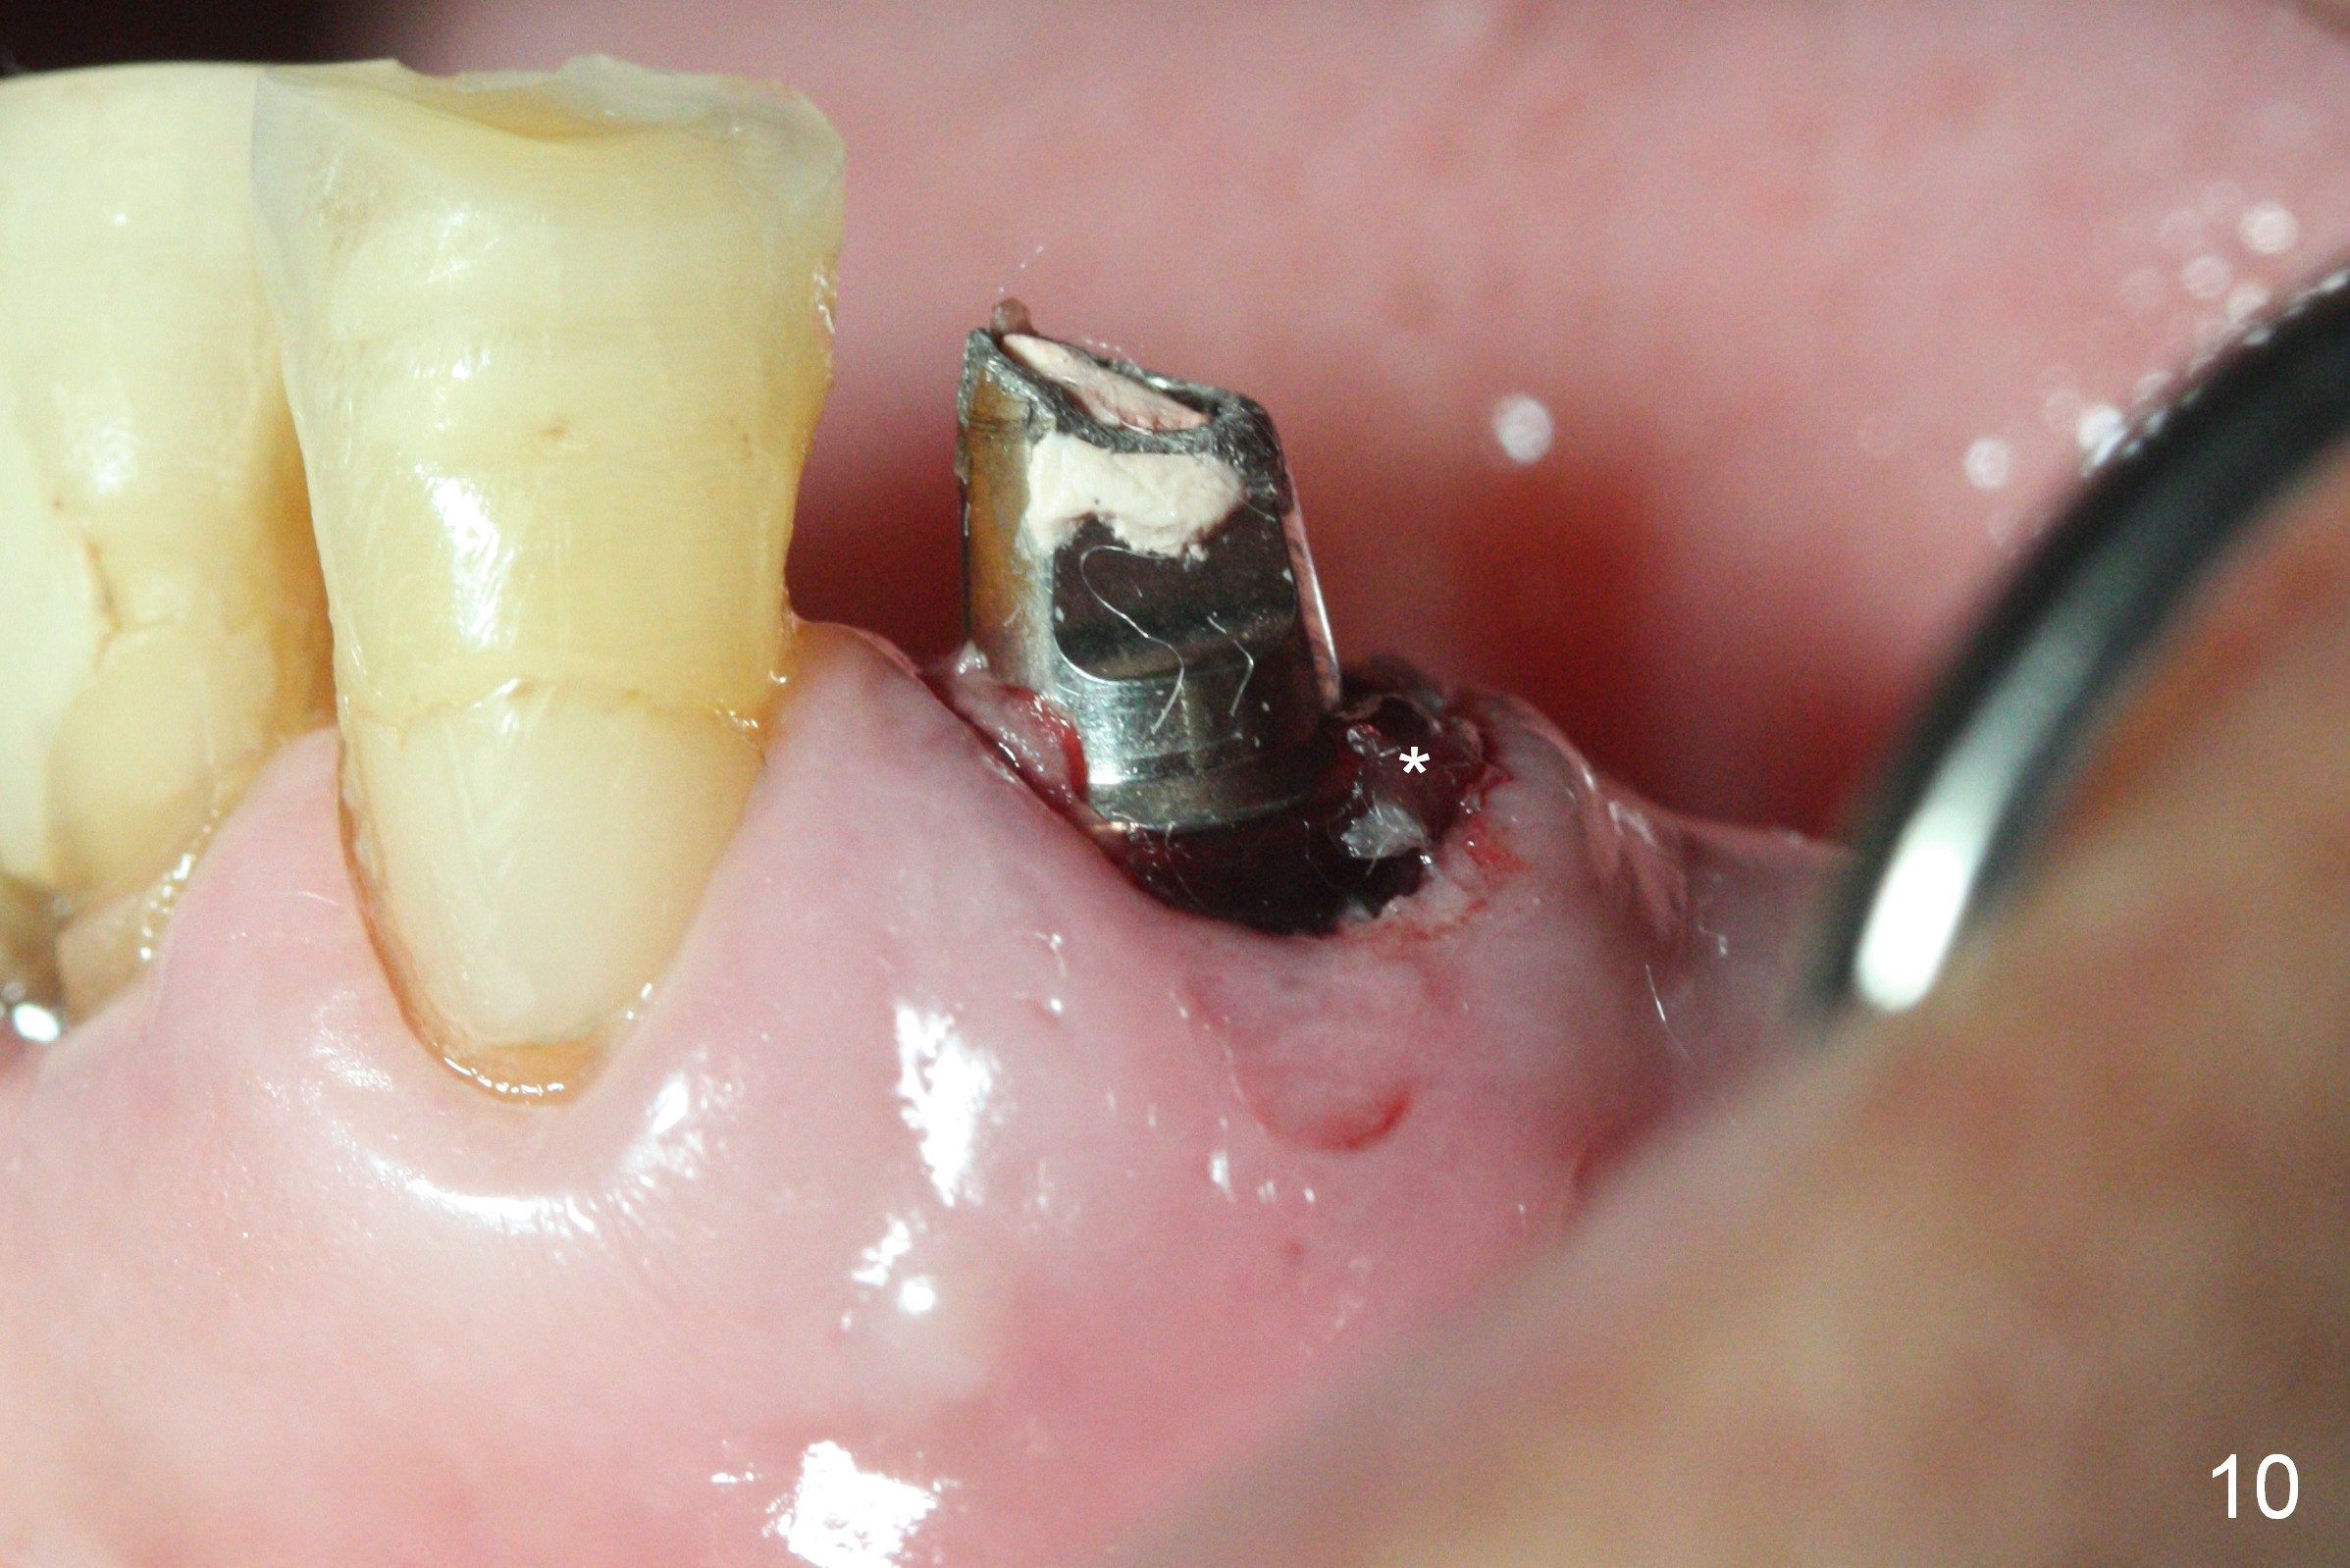

The patient returns 2 days postop because of hemorrhage (Fig.10,11 * after removal of loose periodontal dressing). Periodontal dressing is repacked (Fig.12). The hemorrhage may be due to incomplete removal of granulation tissue or invasion of the Incisive vessel intraoperatively, although there is no pain or paresthesia postop. Soft food is recommended without the upper complete denture. A provisional is fabricated (Fig.14 P) nearly 3 months postop (after changing the 5.5x5(5) mm abutment to 4.5x5(4) mm, Fig.13) when an implant is being place is #31.